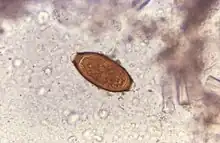

Trichuris trichiura egg

Adult worms are usually 3–5 centimetres (1.2–2.0 in) long, with females being larger than males as is typical of nematodes. The thin, clear majority of the body (the anterior, whip-like end) is the esophagus, and it is the end that the worm threads into the mucosa of the colon. The widened, pinkish gray region of the body is the posterior, and it is the end that contains the parasite's intestines and reproductive organs. T. trichiura eggs are prolate spheroids, the shape of the balls used in Rugby and Gridiron football. They are about 50–54 μm (0.0020–0.0021 in) long and have polar plugs (also known as refractile prominences) at each end.

A stool ova and parasites exam reveals the presence of typical whipworm eggs. Typically, the Kato-Katz thick-smear technique is used for identification of the Trichuris trichiura eggs in the stool sample. Trichuria eggs often appear larger and more swollen on Kato-Katz preparation compared to when using other techniques.[18]

Trichuriasis can be diagnosed when T. trichiura eggs are detected in stool examination. Eggs will appear barrel-shaped and unembryonated, having bipolar plugs and a smooth shell.[20] Rectal prolapse can be diagnosed easily using defecating proctogram and is one of many methods for imaging the parasitic infection. Sigmoidoscopys show characteristic white bodies of adult worms hanging from inflamed mucosa ("coconut cake rectum").[21]